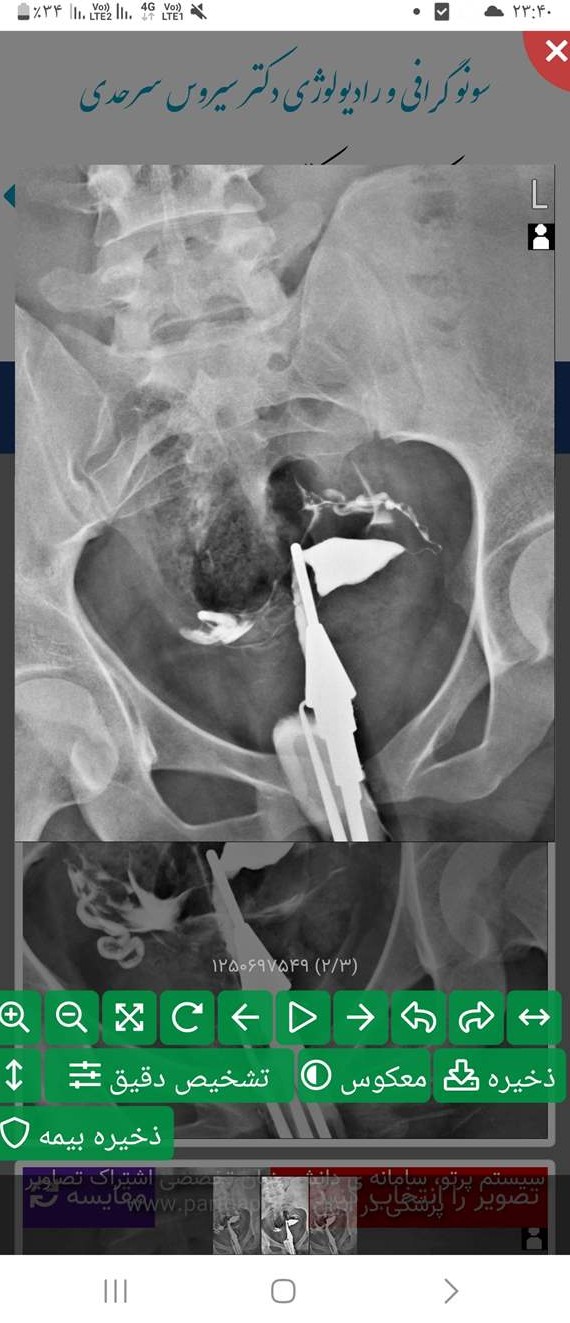

عکس رنگی رحم یا هیستروسالپنگوگرافی یکی از روش های تشخیصی شیوه ی تصویربرداری با اشعه ایکس است که معمولاً برای بررسی آناتومی رحم و لوله ها انجام میشود. عکس رحم

عکس رنگی رحم یا هیستروسالپنگوگرافی روشی است که به منظور بررسی داخل رحم و لوله های رحمی انجام می گیرد و انجام آن در ارزیابی ناباروری بسیار مهم است.

توی توضیحات زده اندازه رحم طبیعی و مایع از هر دوتا لوله خارج شده ولی میترسم چرا عکسه یجوریه😫باردارم الان سکته میکنم نظر شما چیه دکترمم گفت مشکلی نداری